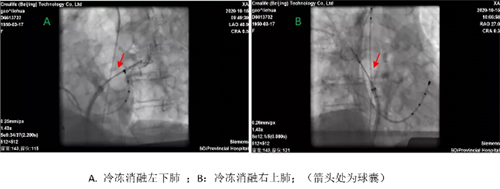

冷冻球囊导管消融流程示意图

冷冻消融中可见肺静脉电位(箭头所示)逐渐延迟后